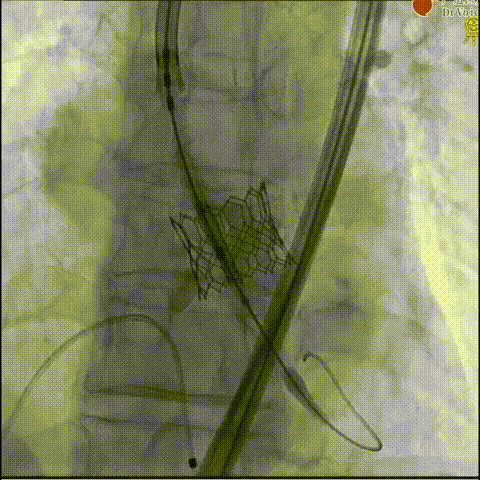

团队首先采用18mm球囊进行预扩处理,为23mm瓣膜输送开辟通路;瓣膜释放阶段,考虑到钙化团块扩张有一定不确定性,为安全起见,通过快速起搏配合减1.5cc容积“downsize”释放策略,实现瓣膜初步精准定位;释放后造影发现瓣周漏,团队随即与GISE主席团专家在线沟通,共同探讨瓣膜后扩优化方案,最终选择增加1.5cc球囊进行后扩,术后瓣周漏明显减少至微量,食道超声确认瓣膜位置、形态及功能均达理想状态,手术取得圆满成功。

球囊后扩

术后食道超声-短轴color

术后食道超声-长轴color

术后造影